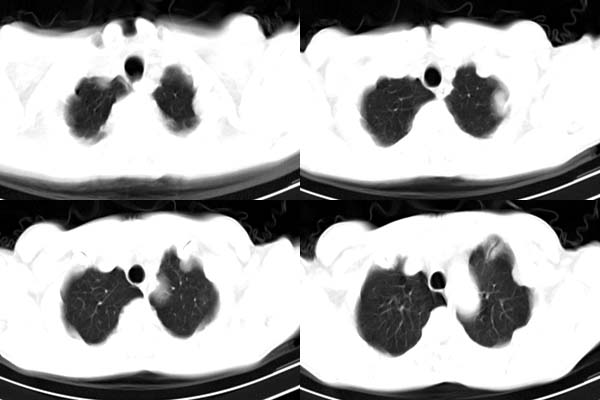

患者,男,65岁,咳嗽,胸痛

胸膜下见多个软组织结节且以宽基底与胸膜相连,上部肋骨似见骨质破坏,考虑:恶性胸膜间皮瘤。

影像表现不再赘述,支持周围型肺癌,伴胸膜转移。排除胸膜原发肿瘤。

说肺癌纵隔窗上不典型,而胸膜间皮瘤却又没胸水。我觉得胸膜间皮瘤放第一位。

左肺下叶周围型肺癌合并左侧胸膜转移

ct所见;左下肺可见片状阴影,密度不均,边缘尚清晰,胸膜方向见有条索相连,纵隔窗未见具体结节。左侧胸膜下见多个软组织结节且以宽基底与胸膜相连,右侧胸锁关节层面亦见软组织结节广基与胸膜相连。纵隔未见肿大淋巴结,气管,支气管开口正常。

影象;1,左下肺感染性病变,结核可能性大。

理由:肺窗显示片影,纵隔窗未能显示具体结节,说明渗出成分为主。建议必要时薄层扫描观察。

2,胸膜病变,以胸膜间皮瘤可能性大。

左肺下叶基底段见结节样稍高密度影,内密度不均匀,边缘不清,可见索条影与邻近胸膜粘连,左侧胸膜上见多个结节影,以宽基底与胸膜粘连.纵隔不宽,内未见明确肿大的淋巴结.

考虑:周围型肺ca伴左侧胸膜转移可能性大 ,不完全除外左肺下叶炎性假瘤,左侧胸膜间皮瘤可能,建议强化ct扫描。

ct所见:左肺上、下叶近胸膜肺外带可见多个大小不等的结节灶,边界清楚,边缘比较光整。近胸膜病灶似与胸膜以宽基底紧连。提供的病史比较简单,我考虑:1、胸膜原发肿瘤可能性大(就形态来看恶性可能性不大);那么大胆的设想一下,左下叶结节是否与它有必然的联系呢?也可以是结核或周围型肺癌。2、还可以考虑为胸膜和肺内的都是转移灶,病人65岁,是不是其他部位的恶性肿瘤转移过来的呢?因为病灶比较表浅,但一侧发病较少见。3、周围型肺癌并胸膜转移的可能性比较小,一是肺内病灶较小,单发,胸膜结节相对较多,位置较远,临近胸膜无受侵。